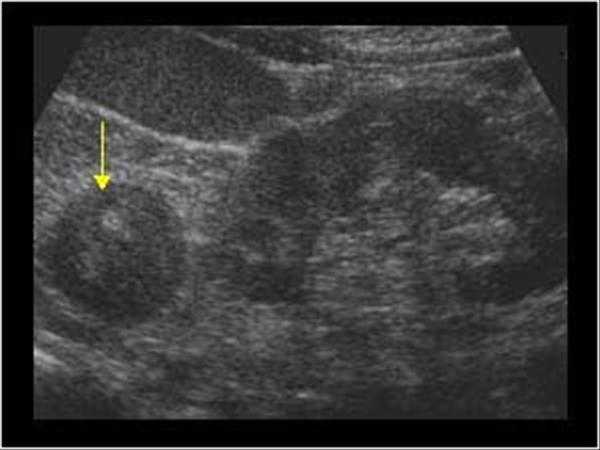

right kidney

Angiomyolipoma

benign fatter renal tumor

80% involve right kidney

echogenicity is gretr than of equal to the renal sinus

right kidney

Angiomyolipoma

benign fatter renal tumor

80% involve right kidney